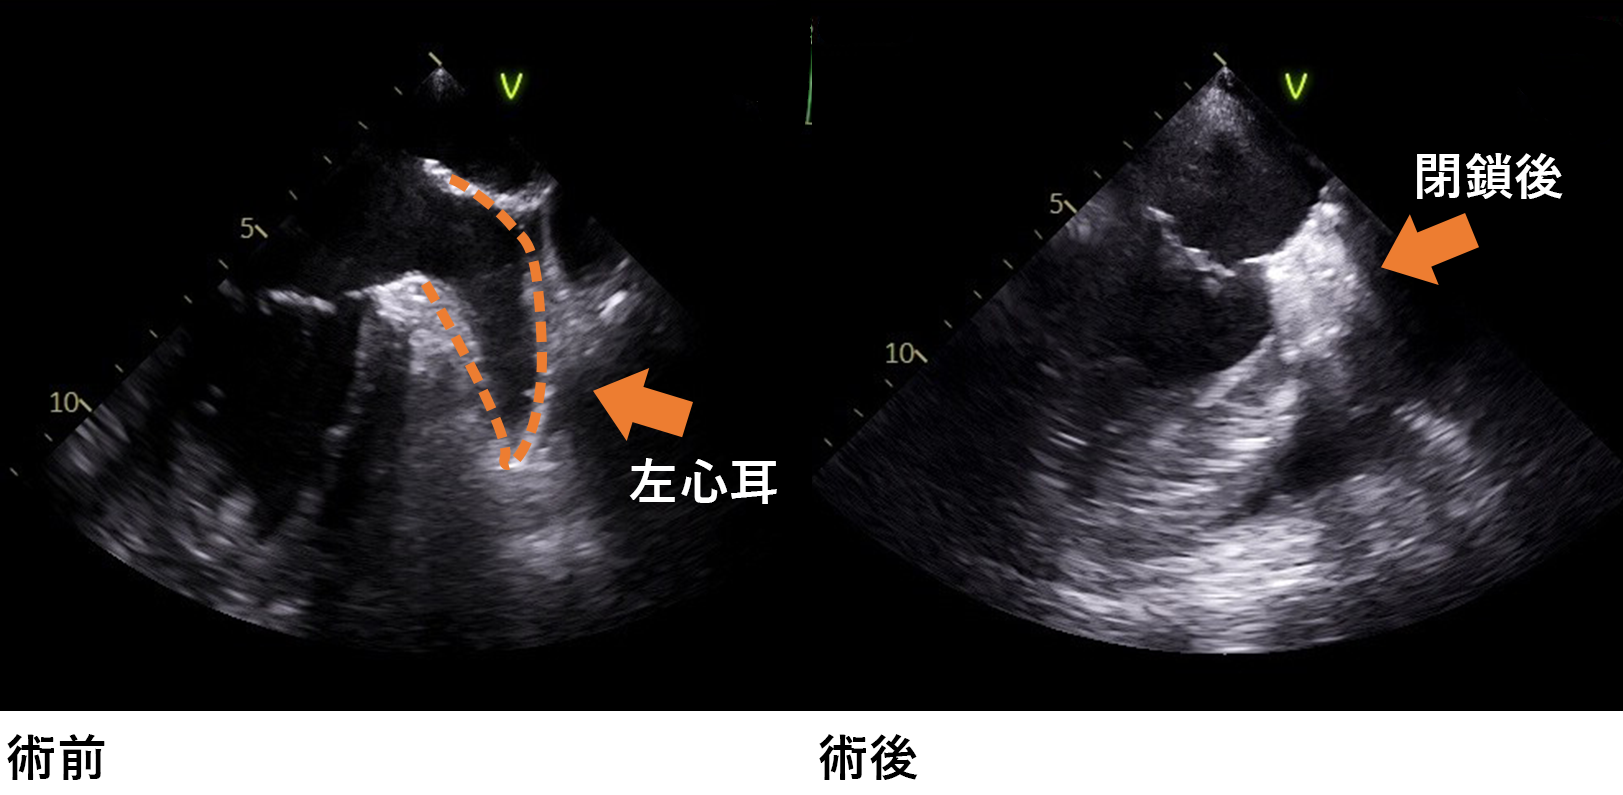

弁膜症

主に大動脈弁や僧帽弁の逆流や狭窄をきたした症例に対して、人工弁と置換したり、自己弁を修復して逆流を停止させる弁形成術を行っております。僧房弁の閉鎖不全症に対しては積極的に弁形成術を行い、自己弁を温存する術式を行っております。 より小さな手術創で低侵襲に手術を行う方法は、最近注目を浴びていますが、当院でも右小開胸や胸骨部分切開による小切開による心臓手術(MICS:Minimally Invasive Cardiac Surgery = 低侵襲心臓手術)も適応のある患者様には行っています。